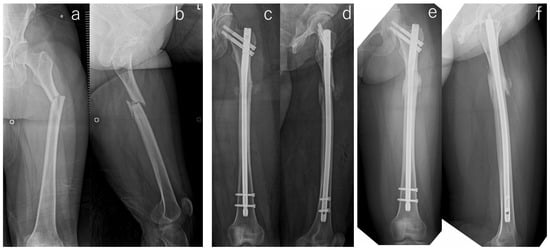

| Implant | Operative Procedure | Adjuvant Therapy | Malalignment | Cortical Discontinuity (-/Direction) | Fracture Gap | Correction Loss | Duration of Bone Union/Nonunion | ||||||

|---|---|---|---|---|---|---|---|---|---|---|---|---|---|

| Open Reduction | Bone Graft | Drilling | LIPUS # | Teriparatide | AP View | Lateral View | AP View | Lateral View | AP View | Lateral View | |||

| Antegrade intramedullary nail | - | - | - | - | - | - | - | - | Posterior | + | - | - | 6 months |

| Antegrade intramedullary nail | - | - | - | - | - | - | - | - | Posterior | + | - | - | 10 months |

| Cephalomedullary long nail | - | - | - | - | - | Varus | - | - | Posterior | - | - | - | Non-union (atrophic) * |

| Cephalomedullary long nail | - | - | - | - | - | - | - | - | Posterior | - | - | - | 16 months |

| Antegrade intramedullary nail | - | - | - | + | - | - | - | - | - | - | - | - | 18 months |

| Antegrade intramedullary nail | - | - | - | + | - | - | - | - | Posterior | - | + | + | Non-union (Hyper) * |

| Antegrade intramedullary nail | + | - | + | + | + | - | - | - | Posterior | + | - | - | Non-union (atrophic) |

| Cephalomedullary long nail | - | - | - | + | + | - | - | - | Posterior | + | - | - | 36 months |

| Antegrade intramedullary nail | - | - | - | + | + | - | - | - | Posterior | + | - | - | 10 months |

| Cephalomedullary long nail | + | + | + | + | - | - | - | - | - | + | - | - | Non-union (atrophic) * |

| Cephalomedullary long nail | - | - | - | + | + | - | Extension | - | Posterior | + | - | - | 21 months |

| Cephalomedullary long nail | - | + | + | + | + | Varus | - | - | - | - | - | - | 6 months |

| Cephalomedullary long nail | + | - | - | + | + | - | - | - | - | + | + | - | Non-union (atrophic) * |

| Antegrade intramedullary nail | + | - | - | + | + | - | - | - | - | - | - | - | 20 months |

| Cephalomedullary long nail | + | - | + | + | + | - | Extension | - | Posterior | + | - | - | Non-union (atrophic) * |

| Cephalomedullary long nail | - | - | - | + | + | - | - | - | - | - | - | - | 6 months |

| Antegrade intramedullary nail | - | - | - | + | + | - | - | - | - | + | - | - | 9 months |

| Antegrade intramedullary nail | + | - | + | + | + | - | - | - | - | - | - | - | Non-union (atrophic) |

| Antegrade intramedullary nail | - | - | - | + | - | Varus | - | - | Posterior | - | - | - | 5 months |

| Antegrade intramedullary nail | - | - | - | + | + | Varus | - | - | - | + | - | - | 8 months |